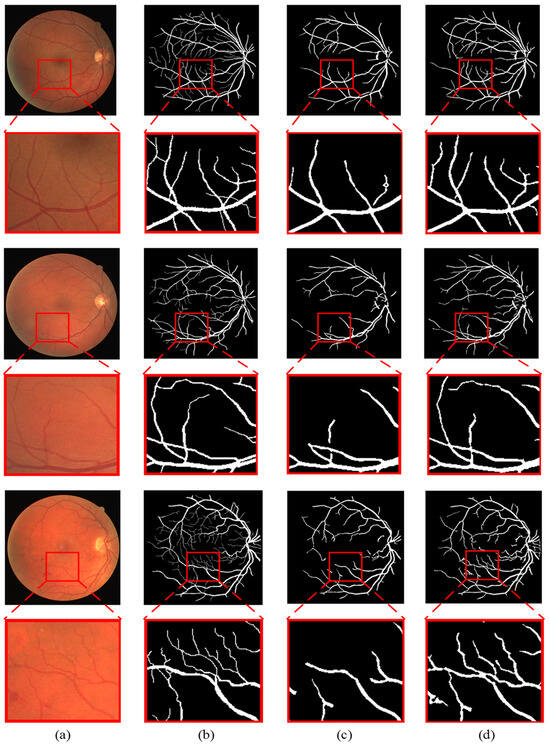

Figure 7 shows the visualized segmentation results of the proposed method on partial images from the DRIVE, STARE and HRF datasets.

To better illustrate the advantages of the proposed method, the segmentation results under the ground truth, the traditional gray-level co-occurrence matrix (GLCM) model and the novel gray-level co-occurrence analysis adaptive (GLCAA) model are compared. Figure 8 and Figure 9 present enlarged comparisons of different models’ segmentation results of partial images from the DRIVE and STARE datasets. Panels (a)–(d), respectively, depict the original input image, the ground truth, segmentation results under the traditional GLCM model, and segmentation results under the novel GLCAA model. From the figures, it can be observed that in the segmentation results based on the traditional GLCM model, many thin blood vessels are not detected. In contrast, the segmentation results obtained using the proposed method closely resemble the ground truth, with many subtle thin blood vessels being detected. Additionally, for the STARE dataset, most retinal images contain varying degrees of pathological features. The proposed method accurately detects both thick and thin blood vessels while also effectively removing much of the noise interference.

Figure 8. Magnification and comparison of segmentation results of different algorithms on DRIVE: (a) the original image, (b) the ground truth, (c) segmentation results under the traditional GLCM model, (d) segmentation results under the novel GLCAA model.

Sensors 24 04326 g008

Figure 9. Magnification and comparison of segmentation results of different algorithms on STARE: (a) the original image, (b) the ground truth, (c) segmentation results under the traditional GLCM model, (d) segmentation results under the novel GLCAA model.